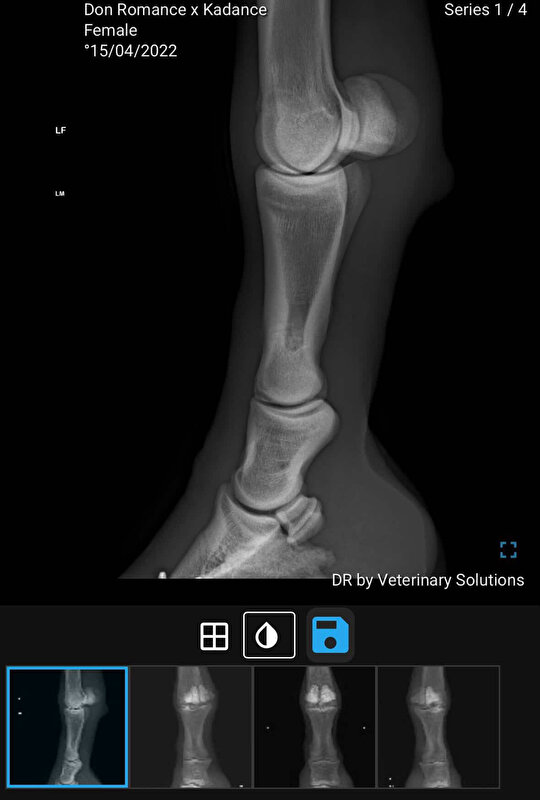

Op 23-01- 2026 heb ik mijn paard van bijna 4 jaar jong met spoed naar de kliniek gebracht, ze kon niet meer lopen en enkel hinken. Zelfs steunen op dat been in rust wou ze niet. Daar haar op stal gezet en ‘s middags hebben de dierenartsen naar haar gekeken. Ze dachten toen aan bot trauma doordat er ook van buitenaf een beste bult aanwezig was op haar linker voorbeen koot en ze daar allerlei veranderingen op zagen botremodellatie met milde osteolyse. Advies was (optioneel) Shockwave om verdere botremodellatie te beperken en het herstel te ondersteunen, 3 sessies en na 6 weken controle. Uiteraard alles gedaan voor herstel.

Mijn merrie is nog maar bijna 4 en verder eigenlijk harstikke gezond, ja ze heeft een bokhoefje maar deze wordt vakkundig bijgehouden elke 6 weken in de kliniek en is geen belemmering. Van binnen heeft deze er ook altijd goed uitgezien (nog steeds). Het is mij en ook de dierenartsen een raadsel hoe ze hieraan gekomen is want ze heeft door haar bokhoefje regelmatig op de röntgen gestaan en daardoor was er ook veel vergelijkingsmateriaal.

Eerste foto is op 23-01 en tweede op 06-03